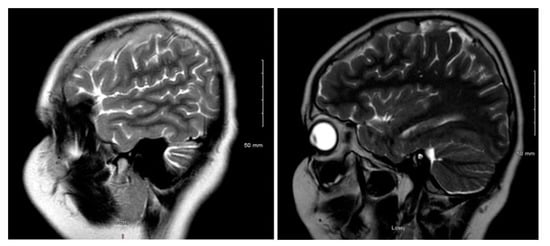

Figure 1 and Figure 2 reveal a change in signal of arachnoid cyst suggestive of interval hemorrhage with a thin subdural hematoma along its inferior aspect. Minimal edema in the subjacent Rolandic cortex was present. Given the patient’s stroke-like presentation, an MRA of head and neck was administered, which was found to be normal. The findings, with a comparison of the previous MRI of the patient at age 4 (Figure 3 and Figure 4), are consistent with a ruptured arachnoid cyst. No acute neurosurgical intervention was performed due to the absence of raised intracranial pressure and reduction of neurological symptoms. A routine EEG performed in the emergency department exhibited interictal epileptiform discharges over the left and right central–temporal region during drowsy and sleep states, suggestive of increased risk for partial seizures from these regions.

Figure 1. MRI T2WI, sagittal section in 2019 (11 years of age).

Figure 3. MRI T2WI, sagittal section in 2012 (4 years of age).